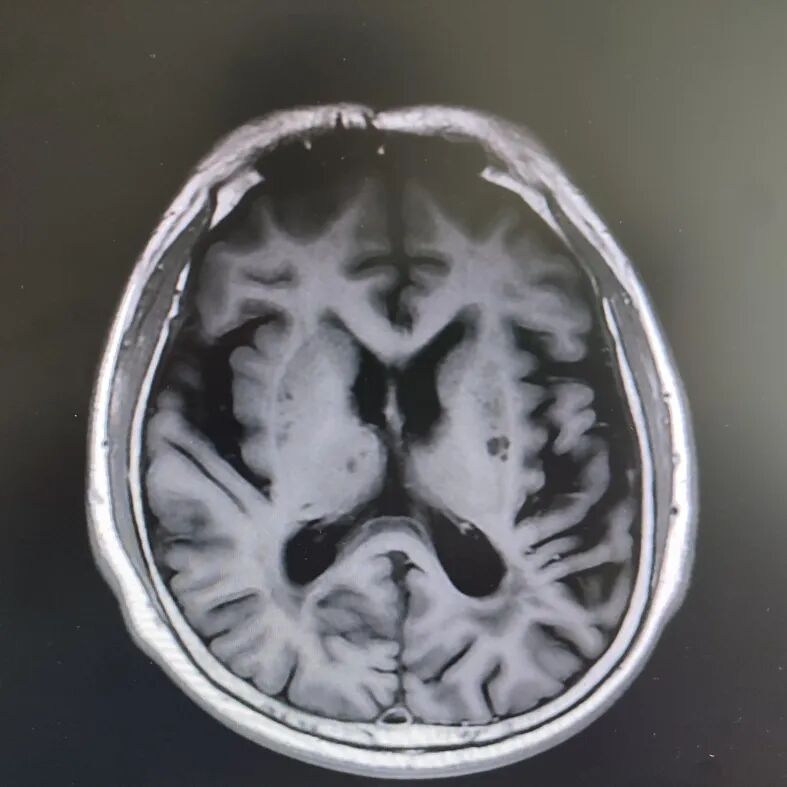

病房里还有另一位患者,来的时候情况更让人揪心:反应迟钝,表情呆滞,行动缓慢。头颅核磁显示脑萎缩明显,但查体发现肌张力、计算力、记忆力、定向力均正常,不符合典型血管性痴呆或阿尔茨海默病表现。

患者头部磁共振影像

凭着多年诊治疑难杂症的丰富经验,赵主任敏锐地意识到这“痴呆”可能是假象,背后另有隐情。他果断建议进一步做特殊感染筛查。果然,检查证实这位患者同样是感染了苍白密螺旋体!经过精准的抗感染治疗,奇迹发生了:患者的反应变快了,眼神灵活了,走路也恢复了正常步态。最终的诊断是“麻痹性痴呆”——一种由神经梅毒引起的、可治疗逆转的“痴呆”类型!